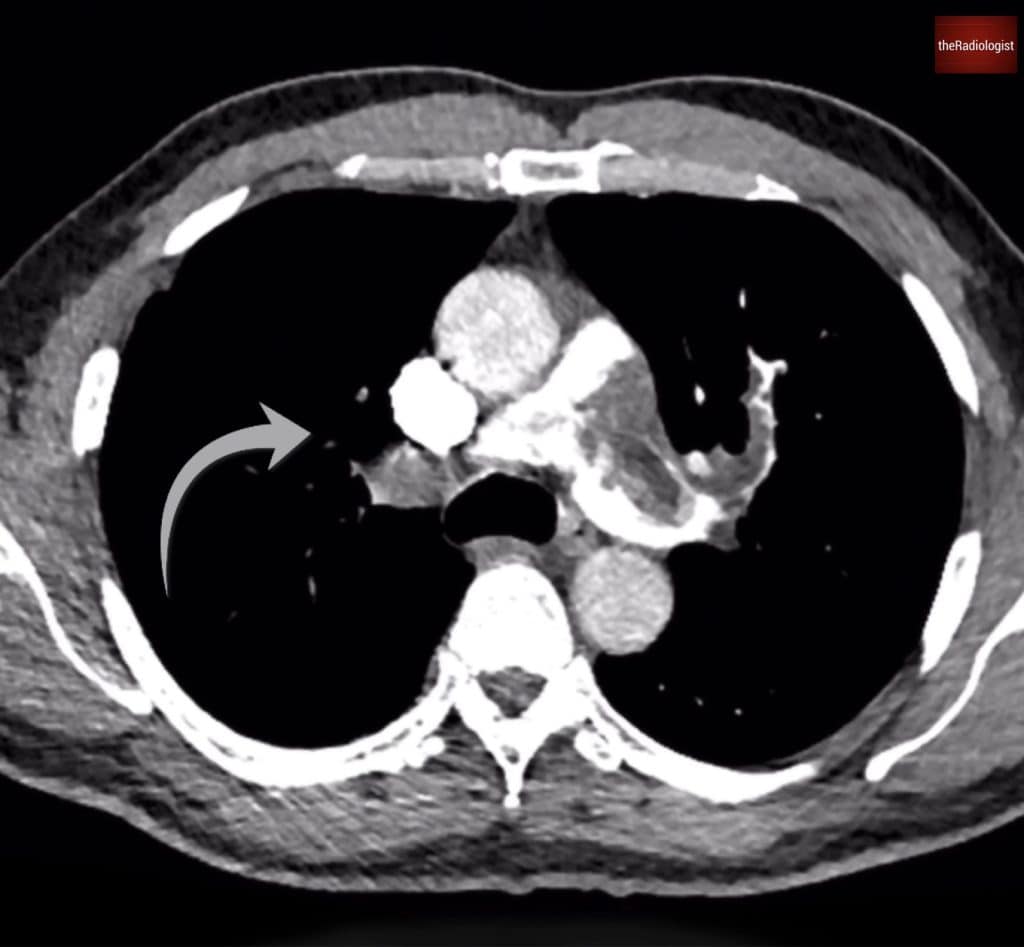

At first glance, the diagnosis seems straightforward: the scan shows extensive central pulmonary artery filling defects, with large filling defects involving the pulmonary trunk, right, and left main pulmonary arteries. Once we see this let’s go through our review areas.

We can see extensive pulmonary artery filling defects within the pulmonary trunk (yellow arrow) extending into both main pulmonary arteries.

Chronic features

However, there are also signs suggesting a chronic component. Some segmental arteries, particularly on the right, appear of reduced calibre or are occluded. These findings shift the differential towards chronic thromboembolic disease.

Pulmonary arteries within the right upper lobe are of reduced calibre suggesting chronic thromboembolic disease.